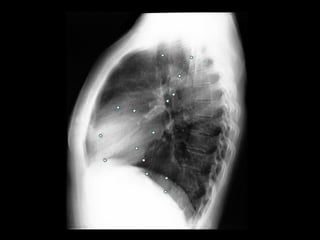

Exames de imagem: Rx Tórax

Primeiro passo na investigação radiológica da

suspeita de HAP;

Achados típicos: aumento do calibre das artérias

centrais, com rápido afilamento dos vasos à medida

que progridem para a periferia;

A área cardíaca pode estar aumentada ou normal;

Calcificação vascular: associado a alta RVP;

Sensibilidade baixa;

Útil para afastar ou sugerir causas de HAP;

Radiografia de tórax normal